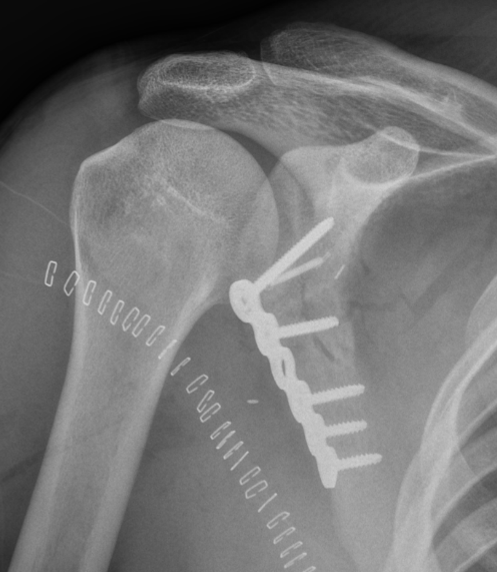

Technique

Plates

- lateral border scapula

- scapula spine

- medial border scapula

Vumedi modified Judet approach combined scapular body and glenoid fracture video

Vumedi extensile Judet approach combined scapular body and glenoid fracture video